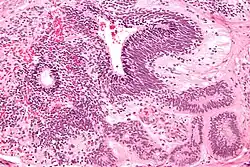

Dysgerminoma

Dysgerminomas are comparable to testicular seminomas and account for approximately 32- 37% of all OGCTs.[1] They are particularly prominent in individuals with dysgenic gonads of 46, XY pure gonadal dysgenesis patients.[1] Based on gross examinations, dysgerminomas are characterized by having a ‘solid, lobulated, tan, flesh-like gross appearance with a smooth surface'.[1] Microscopically, the cellular structure is distinguished by a round-ovoid shape containing ample eosinophilic cytoplasm and an irregularly shaped nuclei.[1] The uniformly positioned cells are separated through the fibrous strands and lymphocytic infiltration is commonly observed.[4]